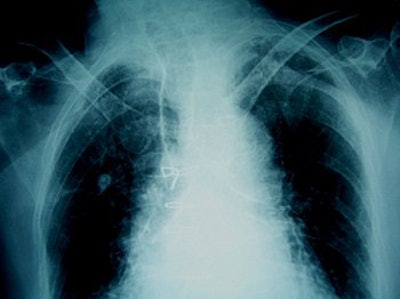

| If the frontal sinuses (above) of an unidentified corpse are intact, they can be as distinctive as fingerprints. Bone spurs (below) can also be unique identifying markers, as these two example x-rays show. Images courtesy of Nancy Adams. |

Adams offered some details on how forensics experts apply imaging to body identification. Frontal sinuses "can be as unique as fingerprints," she said. "You also do the feet. There will be bone spurs on the heels. Another thing is the legs. One individual had a total knee replacement."